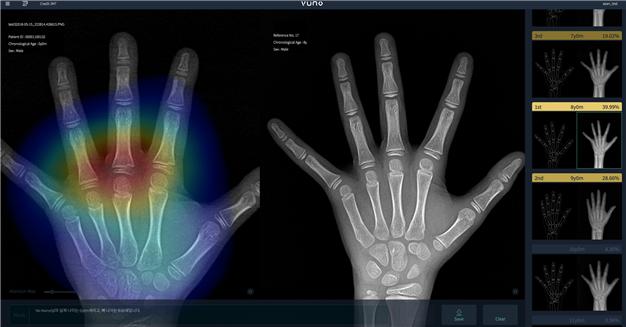

뷰노메드 본에이지는 뷰노가 개발한 인공지능 기반 골연령 진단 소프트웨어다. 성조숙증과 저신장증 등의 검사를 위해 촬영된 수골 X-ray 영상을 인공지능이 자동으로 분석, 의사의 판독 업무를 보조해준다.

서울아산병원과 뷰노가 2017년 미국영상의학학회지에 발표한 임상연구 결과에 따르면 의사가 해당 제품을 이용해 판독한 경우 정확도는 약8% 향상, 판독 시간은 최대 40%까지 감소하는 것으로 나타났다.

뷰노는 국내 대형병원에서 다년간 수집된 X-ray 영상 수 만 건을 인공지능에 학습시켜 의사를 보조할 수 있는 수준의 판독 능력을 갖는 소프트웨어 개발에 성공했다. 뷰노 측은 “임상시험 결과 전문의 3명이 판독한 결과와 비교 시 평균 0.08±0.97세의 차이를 보이며 동등성을 입증했다”고 밝혔다.